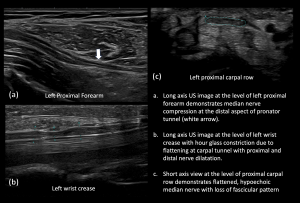

Nerve pathology can present with a variety of imaging appearances, depending on the degree and pattern of injury [7]. Common US findings in peripheral nerve pathology include nerve thickening, loss of fascicular appearance, perineural thickening, hyperemia, notch sign, hourglass constriction, and denervation of muscle groups, as demonstrated in

Fig 9: COMPRESSION UNDER FDS ARCH - Charcot Marie Tooth Disease with superimposed Bilateral Double Crush Syndrome: Compression at Pronator Tunnel and Carpal Tunnel

Fig 10: CHARCOT MARIE TOOTH DISEASE WITH SUPERIMPOSED COMPRESSION AT TWO SITES (DOUBLE CRUSH SYNDROME) Nerve thickening due to underlying hereditary neuropathy

Fig 11: CHARCOT MARIE TOOTH DISEASE WITH SUPERIMPOSED COMPRESSION AT TWO SITES (DOUBLE CRUSH SYNDROME) Compression of Right Median Nerve at the Pronator Tunnel

Fig 12: CHARCOT MARIE TOOTH DISEASE WITH SUPERIMPOSED COMPRESSION AT TWO SITES (B/L DOUBLE CRUSH SYNDROME) Compression of Right Median Nerve at the Carpal Tunnel

Fig 13: CHARCOT MARIE TOOTH DISEASE WITH SUPERIMPOSED COMPRESSION AT TWO SITES (DOUBLE CRUSH SYNDROME) Compression of Left Median Nerve at the Pronator and Carpal Tunnel